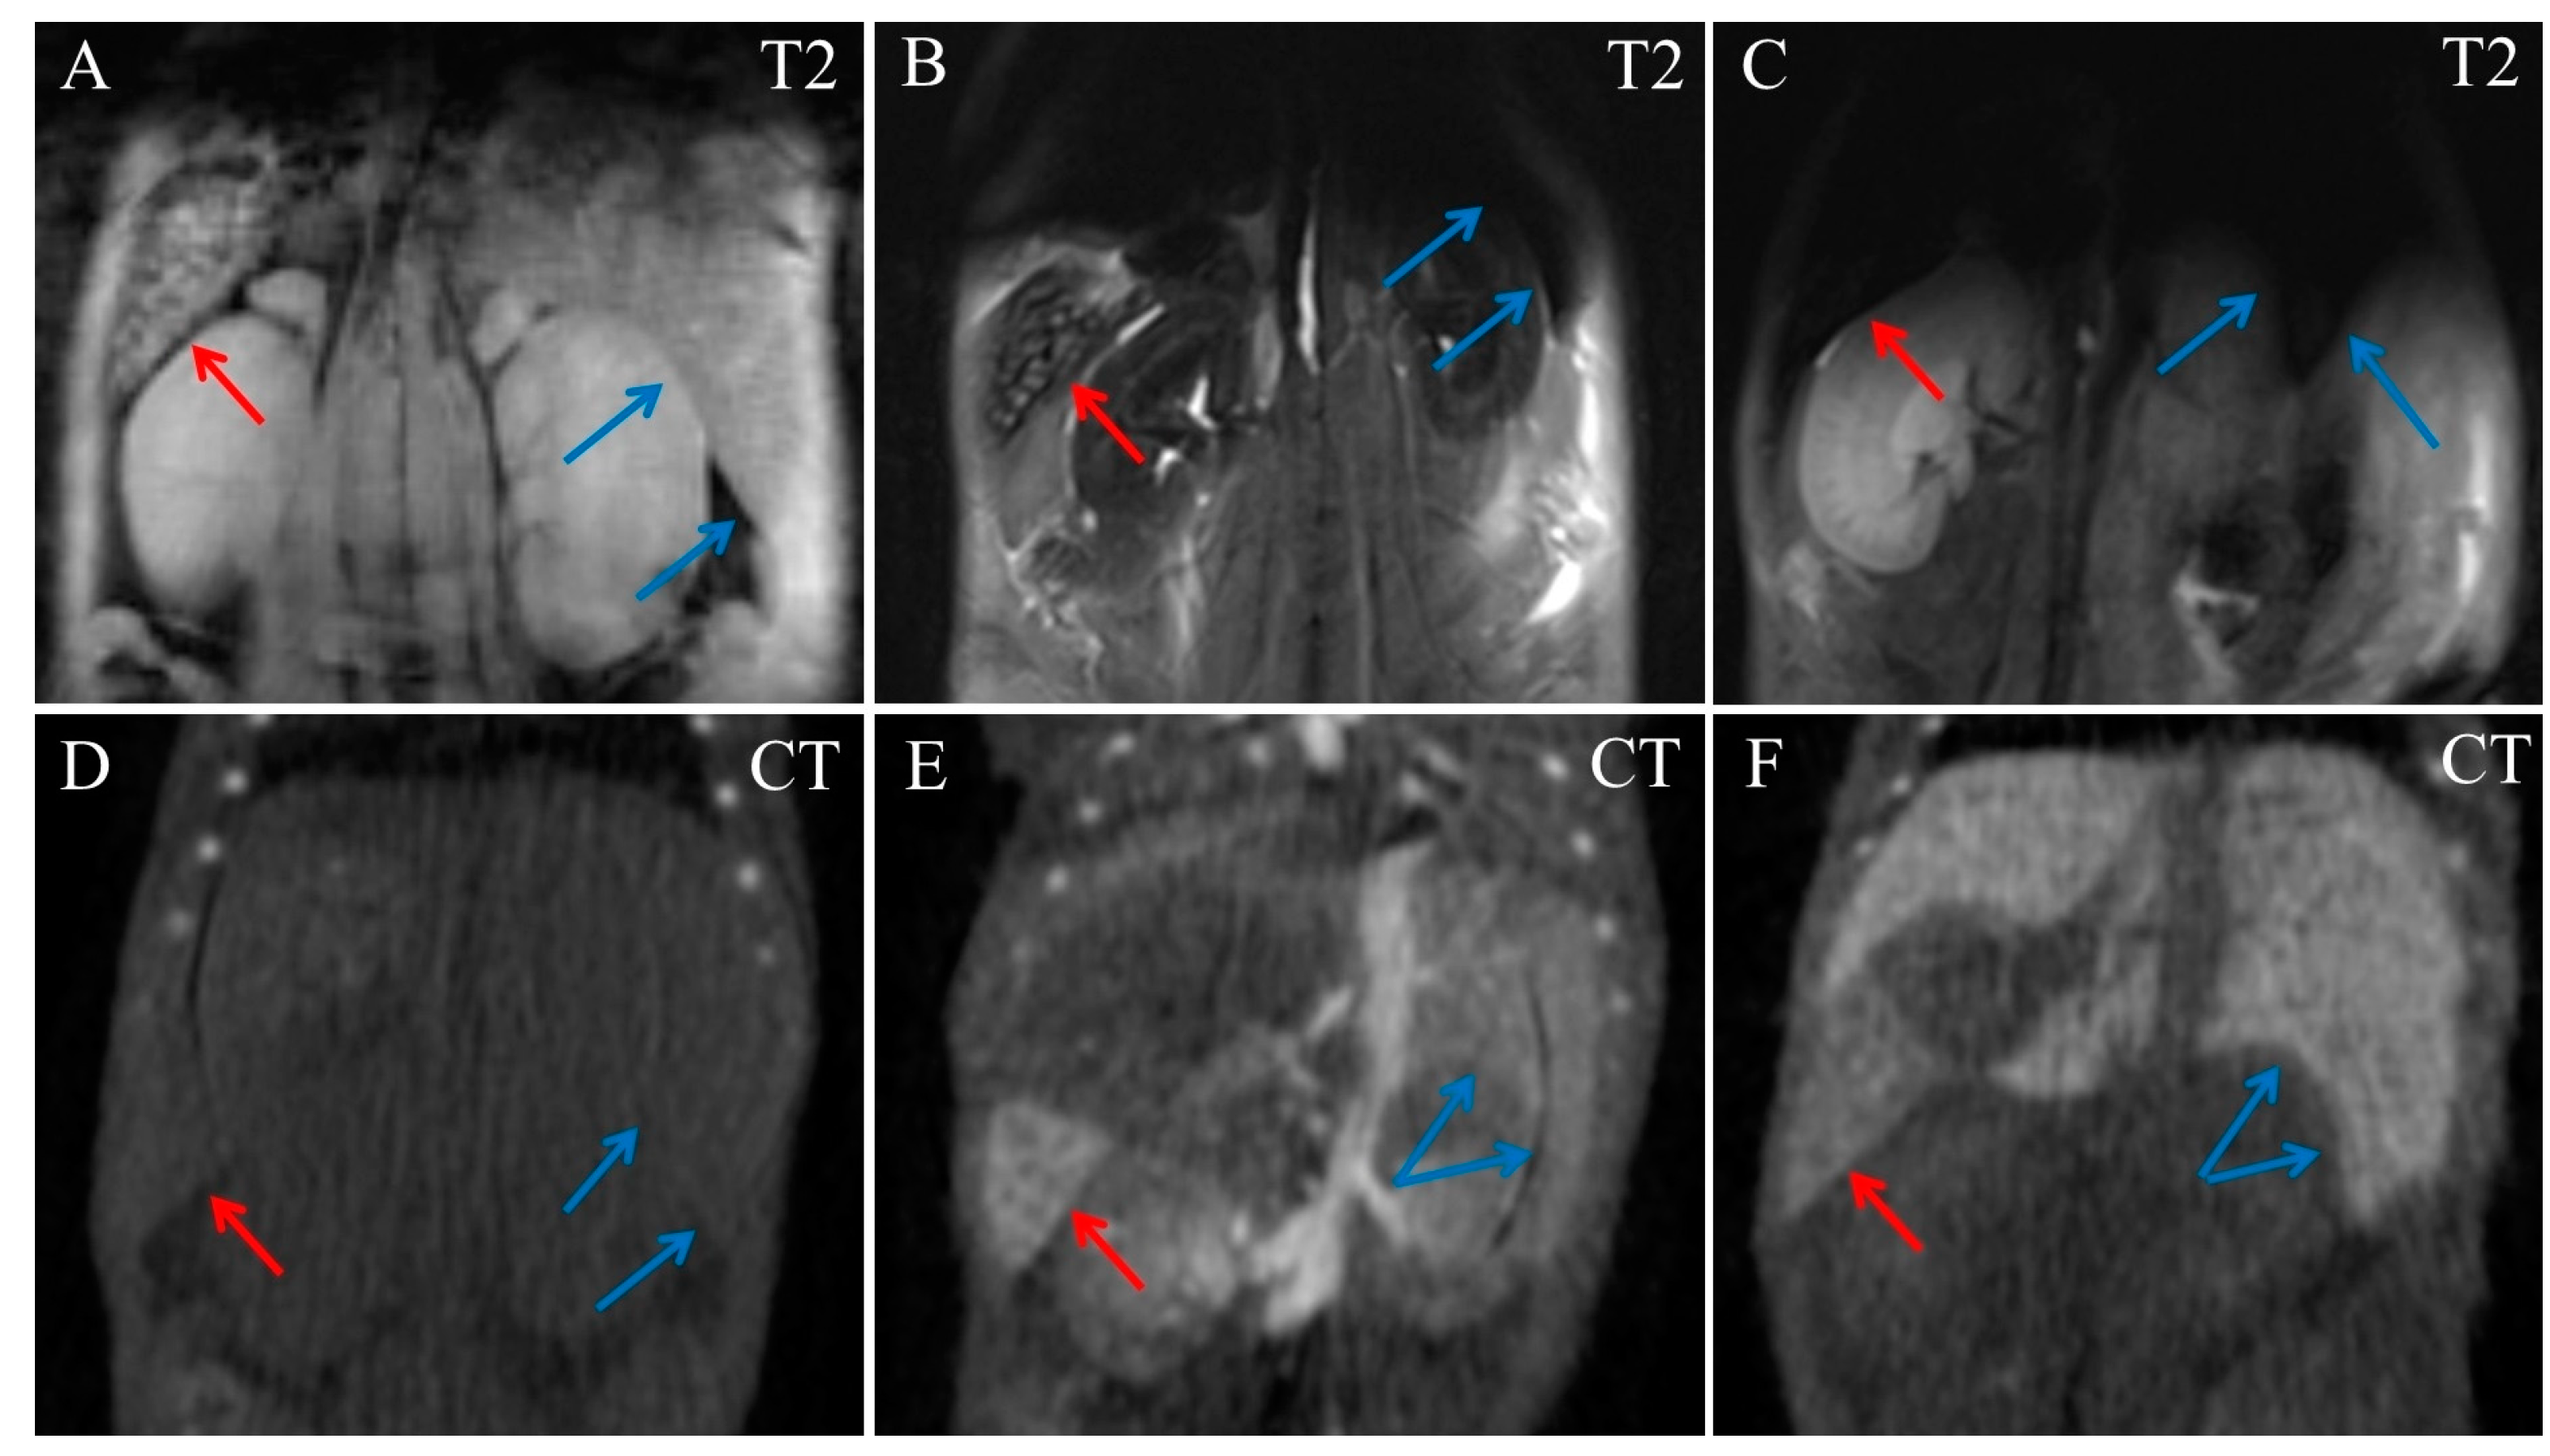

Liver tissues became almost homogenously dark in MRI images even at 5 min post injection (Figure 3B), which did not allow us to distinguish its vessels. In contrast, at 22 min post injection, liver blood vessels were clearly visible in CT images, with the liver tissue itself slightly enhanced (Figure 3E). Liver parenchyma radiodensity increased gradually, reaching its maximum by day 17 post-injection, while the contrast agent had already cleared from its blood vessels (Figure 3F).

Figure 3.

Coronal MRI and CT images of the mouse abdominal area. (A) Native T2 MRI; (B) T2 MRI, 5 min post injection of Fe3O4@Au; (C) T2 MRI, 17 days post injection of Fe3O4@Au; (D) Native CT image; (E) CT image, 22 min post injection of Fe3O4@Au; (F) CT image, 17 days post injection of Fe3O4@Au. Red arrows indicate the spleen, blue arrows indicate margin of the liver.

The spleen also accumulated nanoparticles avidly and was highly hyperdense in CT images and hypointense in MRI, from 5 min to 17 days post-injection (Figure 3). At day 17, gold was observed only in the spleen and the liver, and traces of gold were detected in the kidneys’ parenchyma. Other organs, including the cardiovascular system, returned to baseline completely at this timepoint.